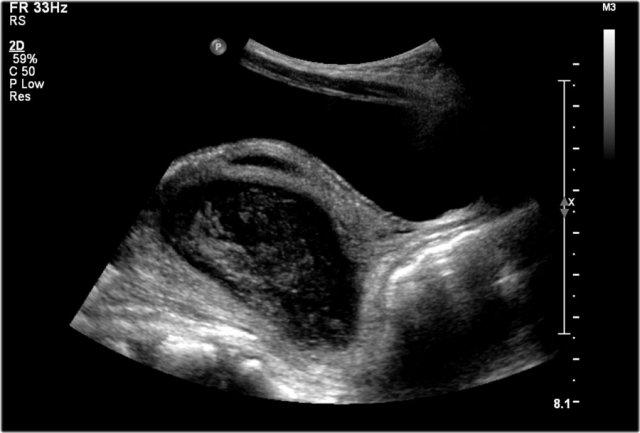

Đây là hình ảnh một nang được phát hiện trước sinh, được xác nhận sau khi sinh ở một bé gái sơ sinh.

Quan sát thấy một nang có mức dịch-dịch (fluid-fluid level).

Trong phẫu thuật, phát hiện xoắn buồng trứng trái.